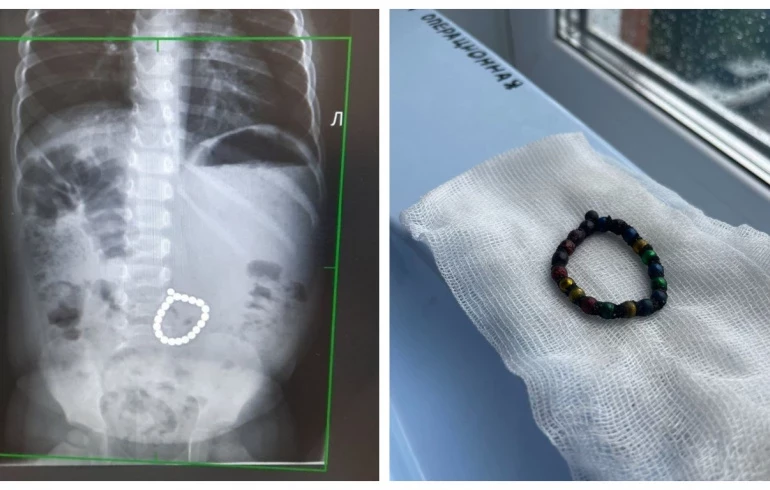

По словам врачей, малыши проглотили магниты, которые впоследствии соединились внутри их брюшной полости, прошёв по ЖКТ. Это привело к нарушению кровообращения и появлению отверстий в кишечнике, через которые содержимое попало в брюшную полость, вызвав перитонит. Медики сразу же провели экстренную операцию, чтобы спасти жизни детей.

По информации пресс-службы Министерства здравоохранения по региону, состояние обоих пациентов стабилизировалось, и они идут на поправку. Медики медучреждения обратились к родителям быть более внимательными при выборе игрушек для детей.